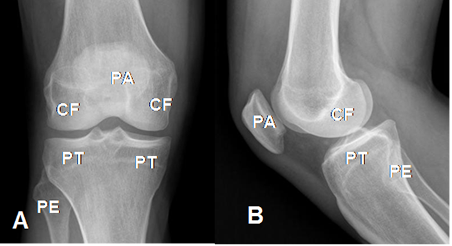

La rodilla se explora con proyecciones AP y lateral y en casos especiales su utilizan radiografías oblicuas o proyección de túnel. (Fig 4 y 5).

Fig 4. Estructuras óseas.

A: Rx AP y B: Rx lateral. PA: Patela. CF: Cóndilos femorales. PT: Platillos tibiales. PE: Cabeza del peroné.